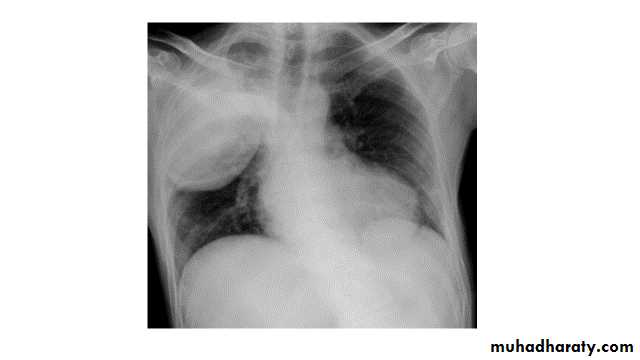

Left upper lobe collapse has distinctive features but can be challenging to identify on chest radiographs by the uninitiated.

Radiographic features

The left upper lobe collapses anteriorly becoming a thin sheet of tissue apposed to the anterior chest wall, and appears as a hazy or veiling opacity extending out from the hilum and fading out inferiorly . It thus reverses the normal slight increase in radiographic density seen as you move down the lung (due to increased thickness of the chest soft tissues).

Parts of the normal cardiomediastinal contour may also be obliterated where the left upper lobe, particularly the lingula abut the left heart border. The anterior parts of the aortic arch are also often obliterated from view.

In some cases the hyperexpanded superior segment of the left lower lobe insinuates itself between the left upper lobe and the superior mediastinum, sharply silhouetting the aortic arch and resulting in a lucency medially. This is known as the HYPERLINK "http://radiopaedia.org/articles/luftsichel-sign" luftsichel sign.

The left hilum is also drawn upwards, resulting in an almost horizontal course of the left main bronchus and vertical course of the left lower lobe bronchus.

Non-specific signs indicating left sided atelectasis will also be present, including:

elevation of the hemidiaphragm

'peaked' or 'tented' hemidiaphragm: HYPERLINK "http://radiopaedia.org/articles/juxtaphrenic-peak-sign" juxtaphrenic peak sign

crowding of the left sided ribs

shift of the mediastinum to the left

On lateral projections the left lower lobe is hyperexpanded and the oblique fissure displaced anteriorly. There is associated increase in the retrosternal opacity.